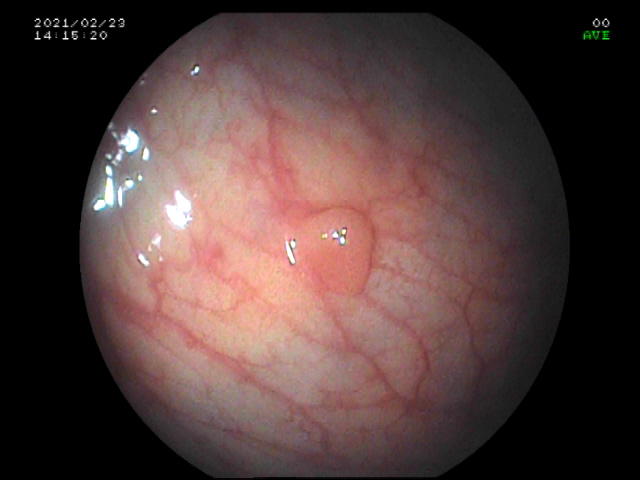

【结直肠息肉】

是常见的消化道疾病,结直肠息肉特别是腺瘤会缓慢进展,发生上皮内瘤变,部分会进展为结肠癌。行结肠镜筛查发现结直肠息肉并行内镜下切除是有效降低结肠癌发病率及死亡率的手段。

直肠息肉

微小及小息肉是结肠镜检最常见的息肉。我院在省内较早开展内镜下结直肠息肉冷切除术,该技术的适应证是结直肠小息肉及微小息肉,对于大小为1-3mm的微小息肉用活检钳直接钳除,对于大小为4-9mm的无蒂息肉应用圈套器勒除。